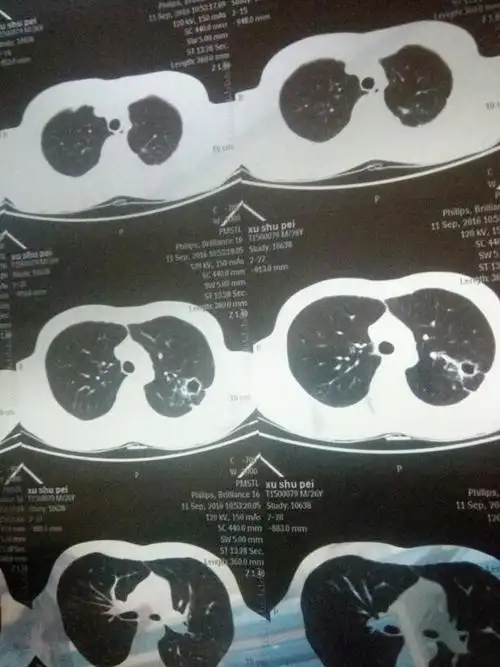

右肺条索状改变

做了一个加强ct 报告如下: 左肺上叶条索状,斑片状高密度影,内见空洞